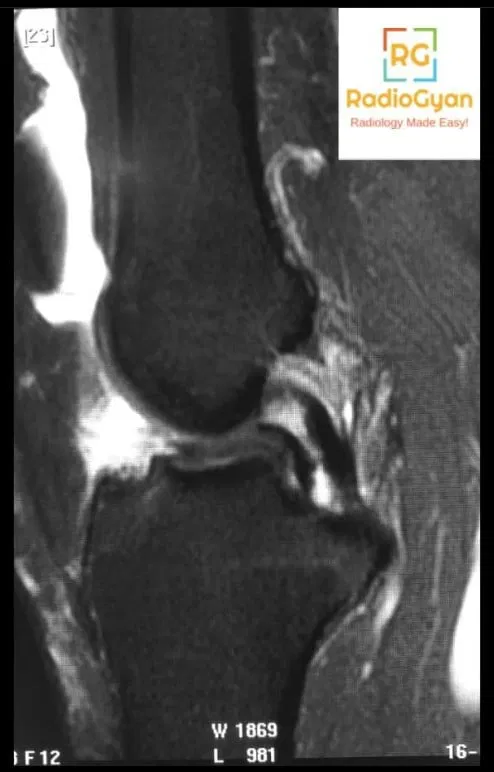

A bucket handle tear is a displaced longitudinal meniscal tear in which an inner central fragment of the meniscus is torn and displaced away from its normal position, typically medially in the lateral meniscus or laterally in the medial meniscus. This lesion is commonly associated with acute knee trauma and often occurs alongside anterior cruciate ligament (ACL) injuries. It leads to mechanical symptoms including joint locking due to the displaced meniscal fragment obstructing normal knee motion.

The meniscus sustains a vertical longitudinal tear that detaches a central fragment, which then displaces into the intercondylar notch, often flipping anteriorly or medially. This displaced fragment creates a mechanical block in the knee joint. On MRI, the tear alters normal meniscal morphology and spatial orientation, allowing the fragment to be recognized by characteristic signs such as the double posterior cruciate ligament (PCL) sign when the displaced medial meniscal fragment lies anterior and parallel to the PCL.

- Double PCL sign (medial meniscus)

- Flipped meniscus sign

- Absent bow tie sign

- Double ACL sign (for lateral meniscus bucket handle tears)

- Meniscal fragment in the intercondylar notch sign